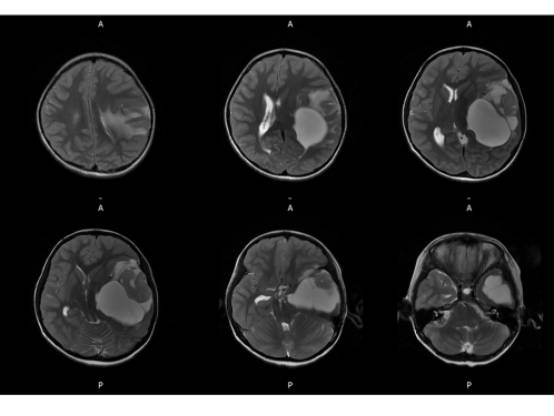

MR平扫及增强示:

左侧颞叶见大块状等长T1等长T2异常信号,FLAIR呈高新,DWI(b=1000)实质部分呈稍高信号,ADC实质部分呈等信号,边界尚清,周围脑实质受压。注入GD-DTPA后病变实质部分呈明显强化。